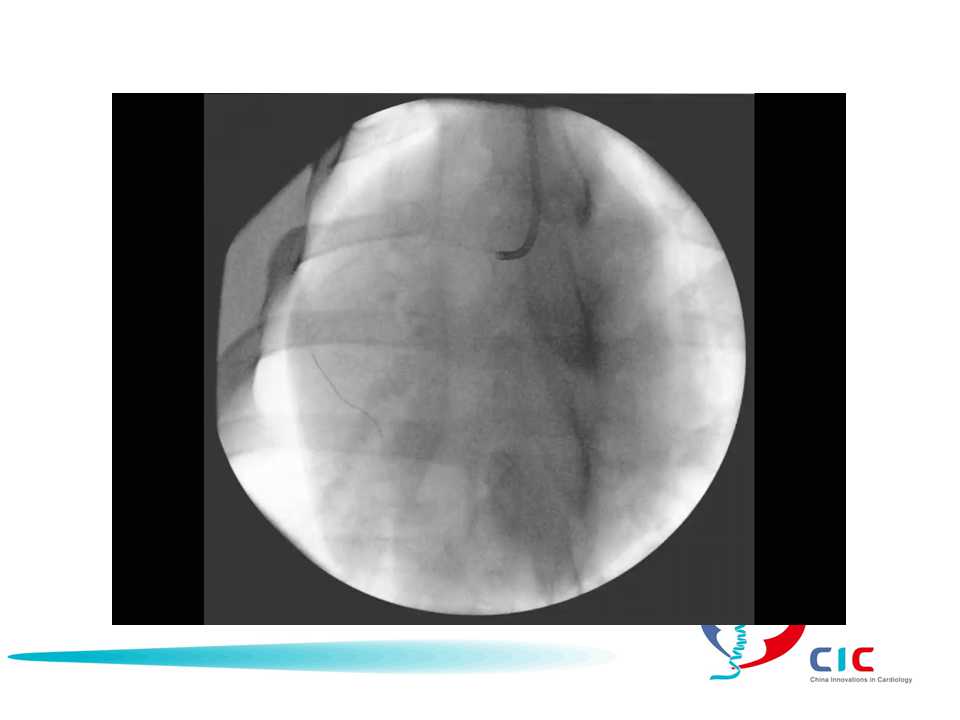

Risk Mitigation at the Point of Disruption Embolic Removal PTA.jpg